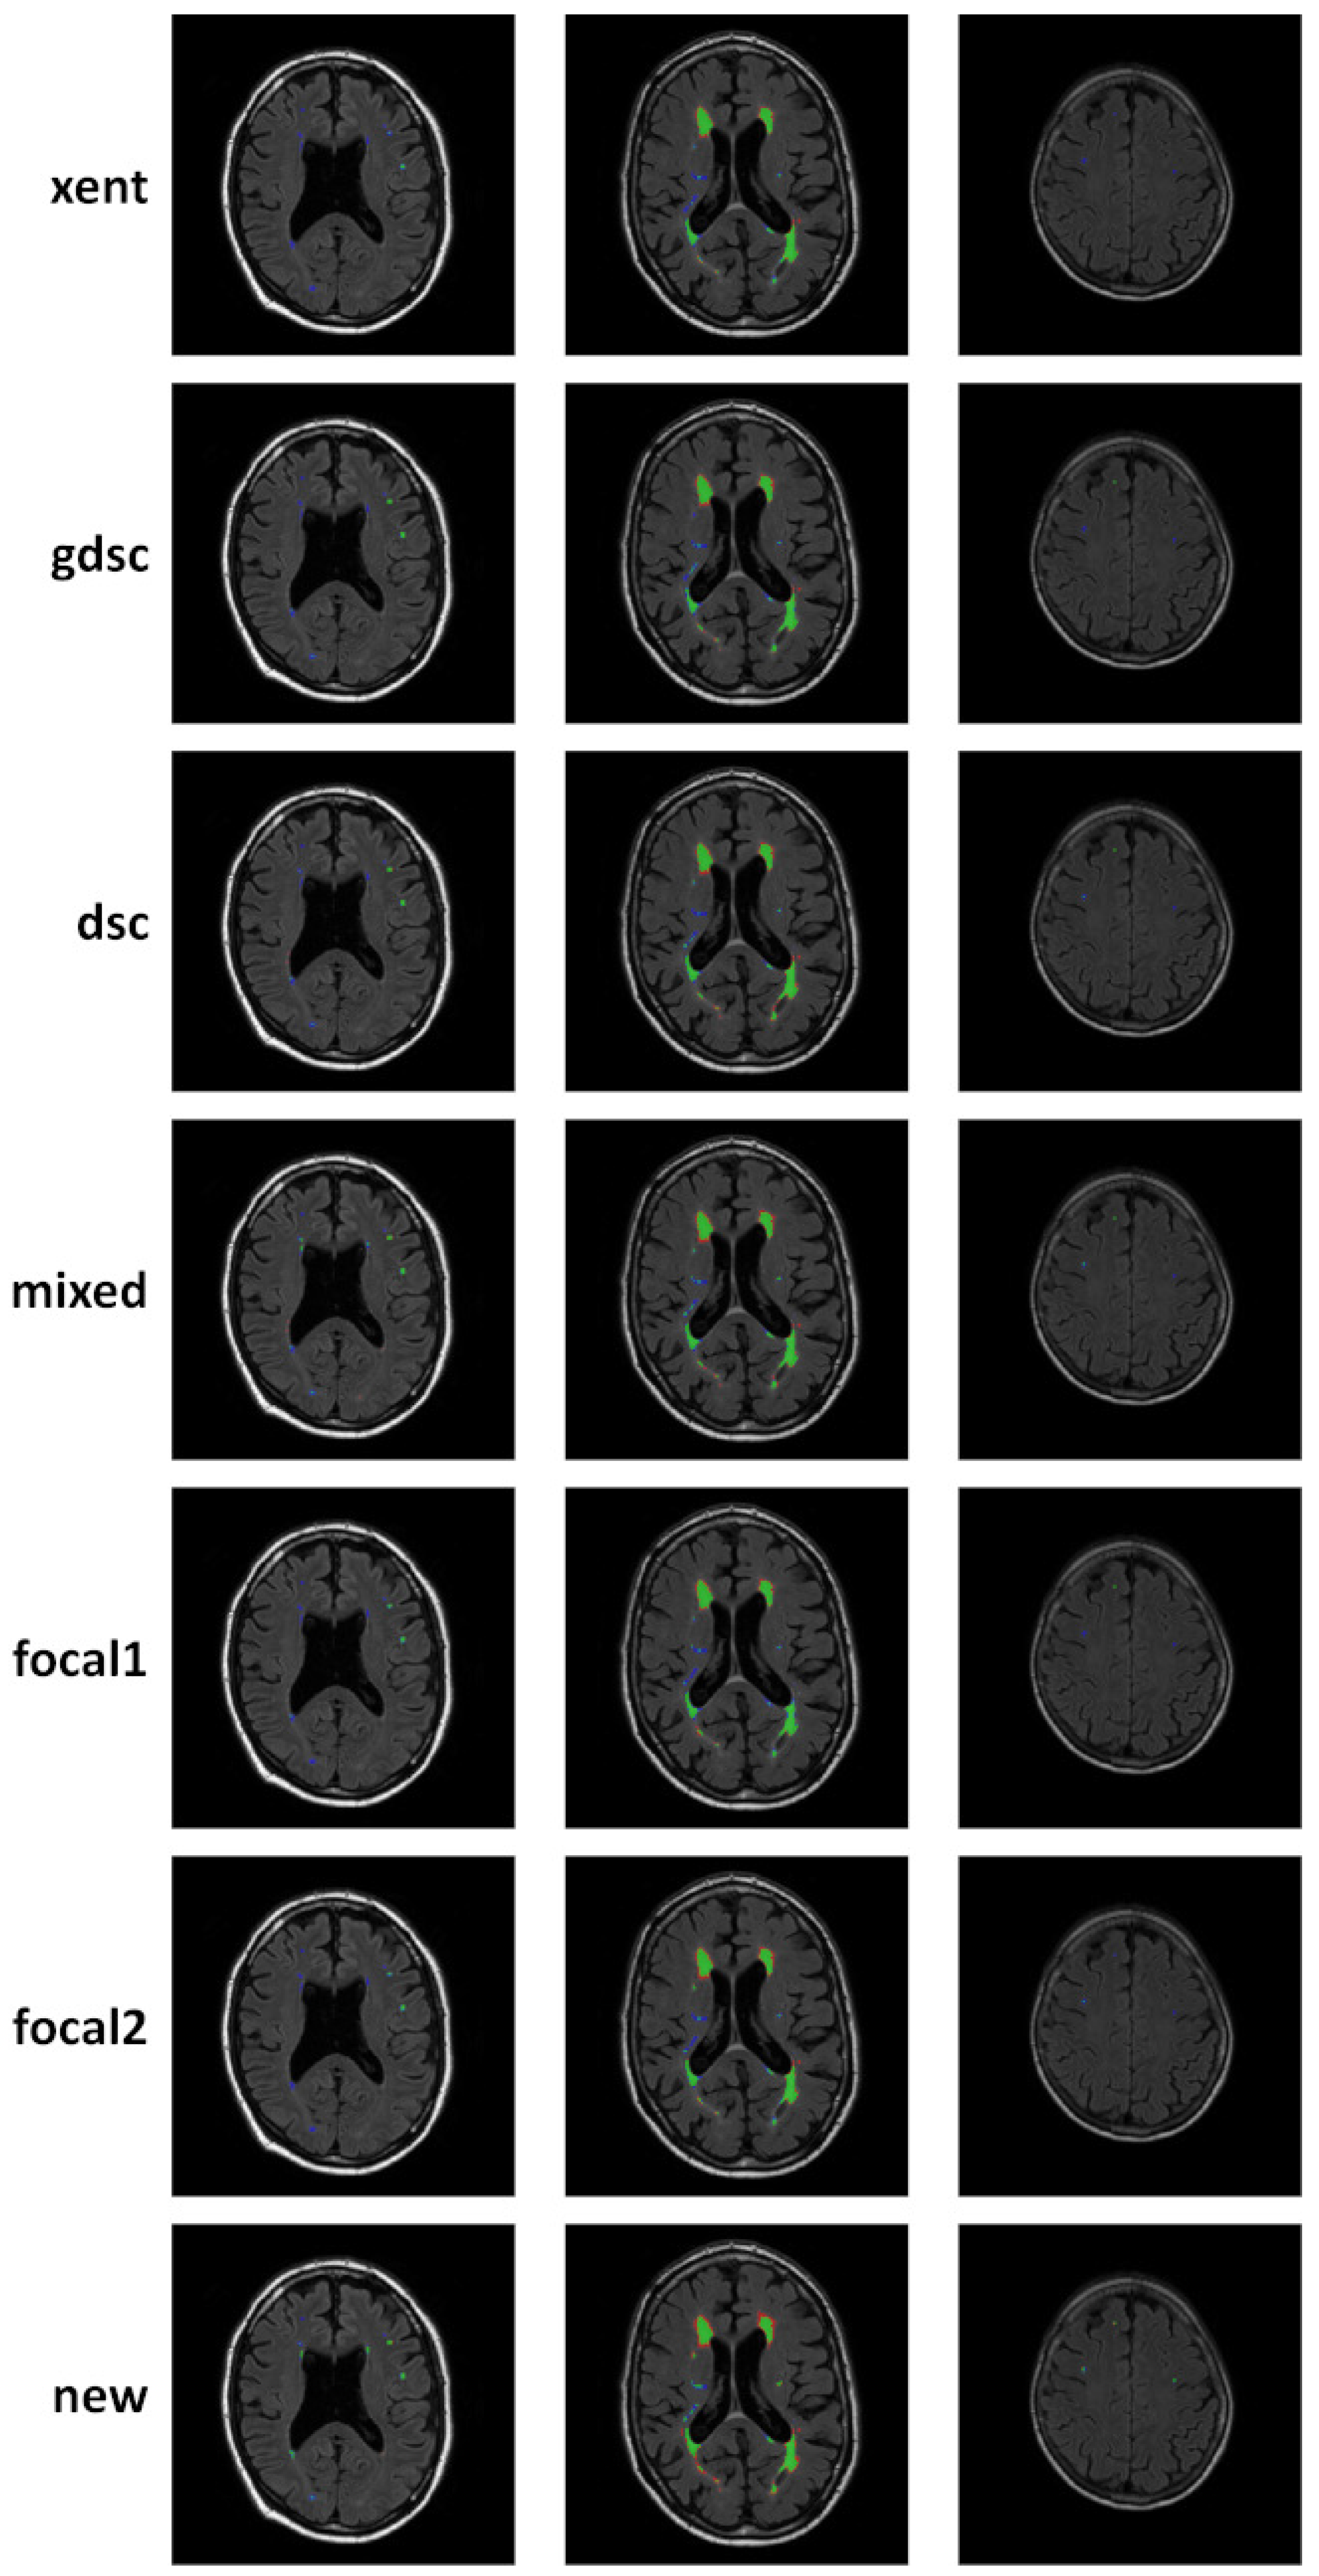

| Loss | Sensitivity () | Precision (P) | |||||||

|---|---|---|---|---|---|---|---|---|---|

| Patch | Train | Test | Patch | Train | Test | Patch | Train | Test | |

| LIT longitudinal dataset | |||||||||

| xent | 0.64 | 0.51 | 0.46 | 0.62 | 0.55 | 0.49 | 0.54 | 0.48 | 0.46 |

| gdsc | 0.93 | 0.54 | 0.53 | 0.96 | 0.81 | 0.77 | 0.82 | 0.20 | 0.29 |

| dsc | 0.96 | 0.55 | 0.52 | 0.99 | 0.89 | 0.84 | 0.54 | 0.29 | 0.24 |

| mixed | 0.93 | 0.55 | 0.54 | 0.98 | 0.86 | 0.82 | 0.74 | 0.18 | 0.24 |

| focal1 | 0.59 | 0.48 | 0.46 | 0.52 | 0.49 | 0.49 | 0.55 | 0.53 | 0.49 |

| focal2 | 0.89 | 0.60 | 0.56 | 0.97 | 0.70 | 0.63 | 0.78 | 0.48 | 0.38 |

| new | 0.79 | 0.58 | 0.56 | 1.00 | 0.94 | 0.90 | 0.36 | 0.14 | 0.23 |